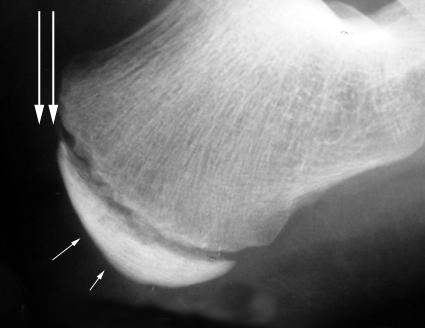

La Enfermedad de Sever o apófisis calcánea es una causa frecuente de dolor en el talón infantil. Suele aparecer entre los 7 y los 12 años de edad y es más frecuente en el género masculino y en aquellos niños que realizan actividad deportiva.

La apófisis calcánea es una inflamación aguda del cartílago por el desarrollo del talón. Durante el periodo de crecimiento se genera tensión muscular en el Tendón de Aquiles y la fascia del pie.

Al tratarse de una patología provocada por la tracción excesiva y repetida del Tendón de Aquiles, el tratamiento irá encaminado a disminuir esa tensión.